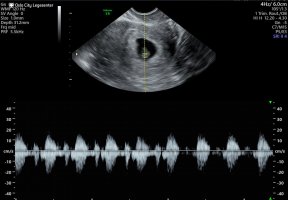

Vis vedlegget 394471Vis vedlegget 394472Ikke bare-bare for en overaktiv hjerne å ha tilgang til ultralyd på jobb! Men her har det heldigvis skjedd ting på bare 5 dagerFørste bildet er 5+0, andre er 5+5. Håper at denne gangen vil det utvikle seg til en ekte, levende baby

Han regnet meg til 6+0 (med forbehold) så en uke tilbake. Ifølge el stemmer dette egentlig bra så kjipt å bli flyttet en HEL uke, men godt å se det var en liten bebis der (og ÉN).

Han sa også at morkaken lå slik til at jeg kunne oppleve blødning, men som ikke var farlig. Han lot dog henvisninga stå åpen så jeg kunne ringe direkte dit og få sjekket det på kort varsel

han sa det slo sakte nå, men kom til å ta seg opp da det nettopp var begynt